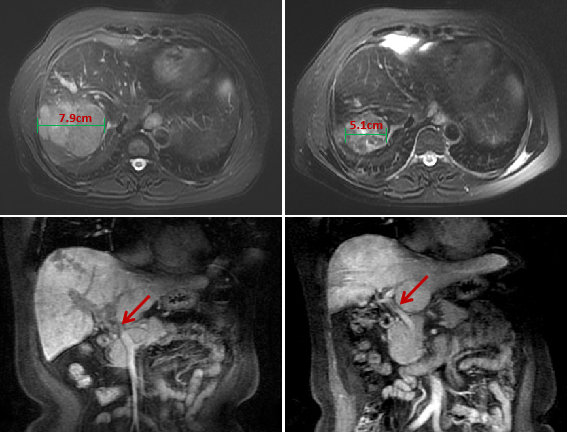

经过两期治疗后,复查核磁共振MR显示病灶缩小明显,门静脉主干癌栓消失,肝功能A级,并且其肿瘤标志物AFP也从2000 ng/mL明显降至16.5 ng/mL。

▲转化治疗后肿瘤缩小、门静脉主干癌栓消失

(左:治疗前;右:治疗后)